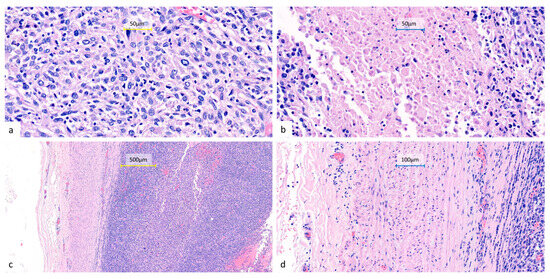

Figure 4. Representative histopathological features of the resected lung tumor. Hematoxylin and eosin-stained sections show sheets of undifferentiated epithelioid to spindle cells (a) (400×) with eosinophilic to amphophilic cytoplasm, marked nuclear pleomorphism, frequent mitoses, and focal necrosis (b) (400×). The tumor infiltrates the pulmonary artery with associated intraluminal tumor thrombi (c) (100×) (d) (200×). All surgical margins are free of tumor involvement, including a bronchial resection margin of 0.8 cm and a pulmonary artery resection margin of 1.0 cm from the nearest tumor invasion. No metastatic involvement can be seen in the sampled peribronchial lymph nodes (0/4) or pleural tissue.